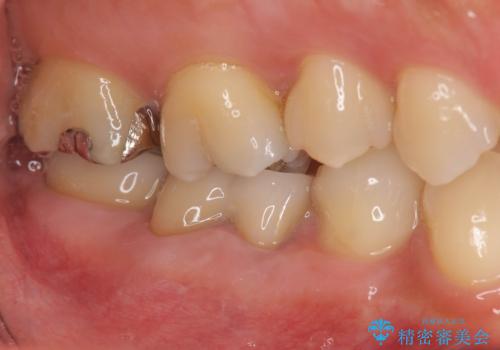

- 「笑った時に目立つ奥歯の銀歯を外して白くしたい。」と希望され来院されました。

金属のクラウンは薄く加工しても壊れないことがメリットですが、セラミッククラウンを装着するにはスペースが少なすぎ、このまま治療を進めると外れやすく壊れ易いセラミッククラウンの設計となるため、歯周外科を行い狭小なスペースの拡大を行うこととしました。